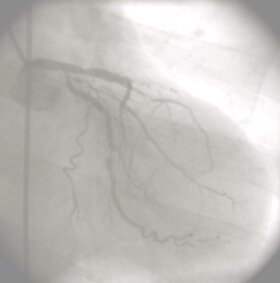

Coronarografia: E' l'esame principale per valutare la malattia delle coronarie. Attraverso un piccolo catetere si procede alla somministrazione di liquido di contrasto direttamente nelle coronarie valutando il grado di ostruzione. Con questa metodica è possibile indagare la pervietà anche dei rami coronarici più piccoli.